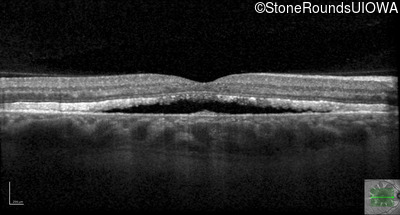

Optical Coherence Tomography - Right - 20/25

Exemplar / OCT Stack

OCT Stack